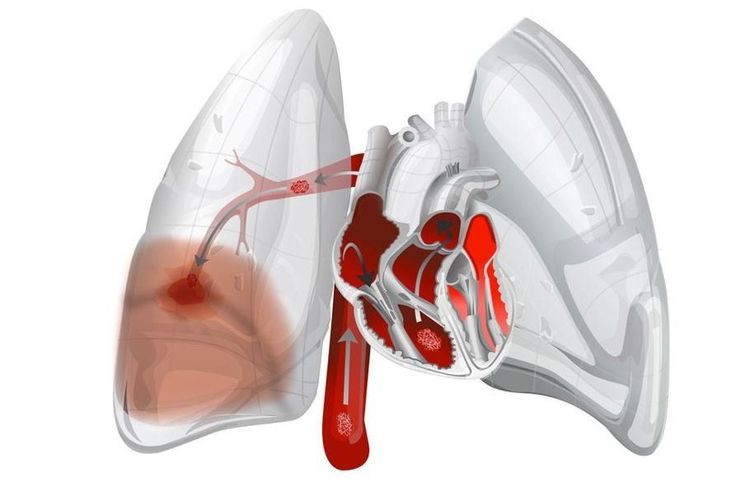

4. Ống thông động mạch phổi (catheter Swan-Ganz)

Ống thông động mạch phổi nổi với một quả bóng ở cuối được giới thiệu vào năm 1970 và từ đó đã trở nên là xu hướng sử dụng trong việc theo dõi các bệnh nhân nguy kịch. Người ta ước tính rằng 2 triệu catheter thăm dò này được đặt cho bệnh nhân hàng năm trên khắp thế giới, tương ứng với chi phí toàn cầu ước tính từ 1 đến 2 tỷ đô la.

Bệnh lý của tuần hoàn phổi

- Suy thất phải

4.2 Biến chứng của ống thông động mạch phổi

- Nhồi máu phổi: bóng vô tình bị phồng ở vị trí xa;

- Vỡ động mạch phổi: sưng bóng trong khi PAC đang ở vị trí bít.

Vỡ động mạch là biến chứng nghiêm trọng nhất (tỷ lệ tử vong gần 50%) và được biểu hiện bằng xuất huyết phế quản thảm khốc. Nguyên nhân là do thiếu kiểm soát khi bơm bóng: luôn đảm bảo có đường cong AP trước khi bơm bóng.Biến chứng nhiễm trùng: tỷ lệ mắc 2-5%; nhiễm trùng da, huyết khối, viêm nội tâm mạc.Tỷ lệ biến chứng nghiêm trọng: <1%.